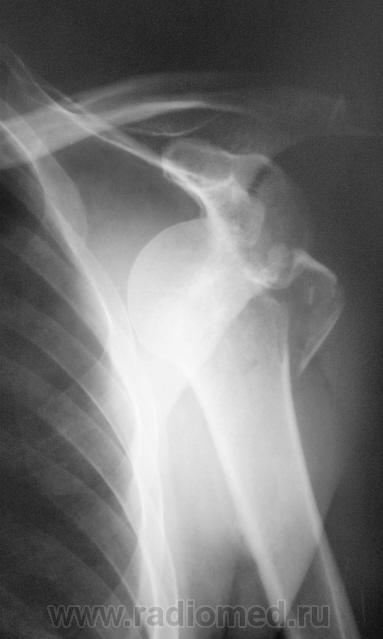

Пол пациента: Мужской пол Тип патологии: Травма Область исследования: Скелетно-мышечная система Методы исследования: Rg Травма. https://radiomed.ru/sites/default/files/styles/case_slider_image/public/user/12/2.p9240060a.jpg?itok=NJ1o5fez ID:20220 Wed, 28/03/2012 - 20:43 #1 Глазков Игорь А... Offline Last seen: 10 months 2 weeks ago Joined: 19.12.2008 - 20:41 Posts: 1597 плечевой кости с отрывом большого бугра. К травматологу и на контроль. Прийди к Себе Wed, 28/03/2012 - 21:04 #2 И.Бондаренко Offline Last seen: 5 days 7 hours ago Joined: 13.09.2011 - 22:55 Posts: 9206 +1. Дополнительно вдавленный перелом головки плечевой кости.

плечевой кости с отрывом большого бугра. К травматологу и на контроль.

+1. Дополнительно вдавленный перелом головки плечевой кости.